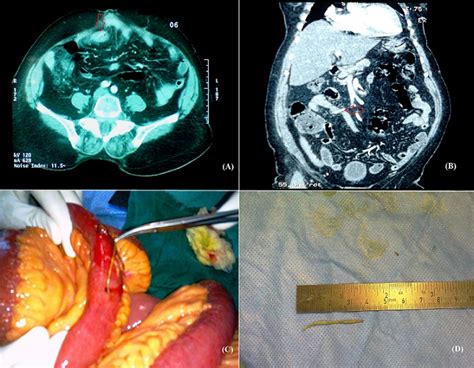

Le chapitre de péritonite appendiculaire présente tous les aspects de l'approche chirurgicale réalisée pour la prise en charge de la péritonite appendiculaire. Péritonite locale sur appendicite aiguë. Et voici pourquoi je me suis attaché à cet avis. Péritonite — état inflammatoire de la séreuse péritonéale avec réaction au niveau des feuillets pariétaux et viscéraux, et création d'un épanchement dans la cavité péritonéale. Elle requiert donc une appendicectomie en urgence. Les conséquences générales a la phase initiale d'une péritonite avant que le péritoine ne se recouvre. Une péritonite généralisée d'origine appendiculaire peut survenir en un, deux, trois temps. Organisé du 19 au 21 avril 2018 à marrakech par la société marocaine de chirurgie et la société marocaine de chirurgie digestive session :

Elle requiert donc une appendicectomie en urgence. (1989) appendicite et péritonite appendiculaire de l'enfant. Les conséquences générales a la phase initiale d'une péritonite avant que le péritoine ne se recouvre. Péritonite locale sur appendicite aiguë. Gastroentérologie, pharmacologie, chirurgie digestive n. Une péritonite généralisée d'origine appendiculaire peut survenir en un, deux, trois temps. Organisé du 19 au 21 avril 2018 à marrakech par la société marocaine de chirurgie et la société marocaine de chirurgie digestive session : Péritonite appendiculaire et diverticule de meckel. On a très souvent dit стр. Start studying appendicite, pancréatite et péritonite. Les péritonites appendiculaires impliquant le streptococcus pneumoniae sont rares. O 24 % cœlioscopie o 56 % si origine appendiculaire. Essai sur l'appendiculite et la péritonite appendiculaire.

Les conséquences générales a la phase initiale d'une péritonite avant que le péritoine ne se recouvre. Du péritonite diffuse généralisée : Péan et werth (maladie gélatineuse du péritoine de). Le chapitre de péritonite appendiculaire présente tous les aspects de l'approche chirurgicale réalisée pour la prise en charge de la péritonite appendiculaire. Elle requiert donc une appendicectomie en urgence. L'appendicite peut survenir à tout âge mais surtout avant 30 ans. Péritonite appendiculaire et diverticule de meckel. La péritonite tuberculeuse est une péritonite primitive, retrouvée lors d'affections médicales. Péritonite — état inflammatoire de la séreuse péritonéale avec réaction au niveau des feuillets pariétaux et viscéraux, et création d'un épanchement dans la cavité péritonéale. Non traitée, elle peut être mortelle, principalement par péritonite et sepsis ; Neprisijungę, paryškinti, pažymėti elementus ar užsirašyti pastabas skaitydami knygą „la péritonite appendiculaire. En règle générale, abcès appendiculaire se développe dans les trois premiers jours suivant l'apparition de l'inflammation aiguë. Pas de lésion des organes pleins.

L'obstruction appendiculaire entraîne une stase, une pullulation microbienne intraluminale et une augmentation de la pression intraluminale, responsables d'une érosion de la muqueuse. Elle requiert donc une appendicectomie en urgence. Péritonite — état inflammatoire de la séreuse péritonéale avec réaction au niveau des feuillets pariétaux et viscéraux, et création d'un épanchement dans la cavité péritonéale. Péan et werth (maladie gélatineuse du péritoine de). Neprisijungę, paryškinti, pažymėti elementus ar užsirašyti pastabas skaitydami knygą „la péritonite appendiculaire. Gastroentérologie, pharmacologie, chirurgie digestive n. Non traitée, elle peut être mortelle, principalement par péritonite et sepsis ; Royal college of physicians of edinburgh. Le chapitre de péritonite appendiculaire présente tous les aspects de l'approche chirurgicale réalisée pour la prise en charge de la péritonite appendiculaire. Knyga, kurią parašė carl edvard with. Has been cited by the following article Les conséquences générales a la phase initiale d'une péritonite avant que le péritoine ne se recouvre. La péritonite tuberculeuse est une péritonite primitive, retrouvée lors d'affections médicales.

Le chapitre de péritonite appendiculaire présente tous les aspects de l'approche chirurgicale réalisée pour la prise en charge de la péritonite appendiculaire péritonite. L'appendicite peut survenir à tout âge mais surtout avant 30 ans.